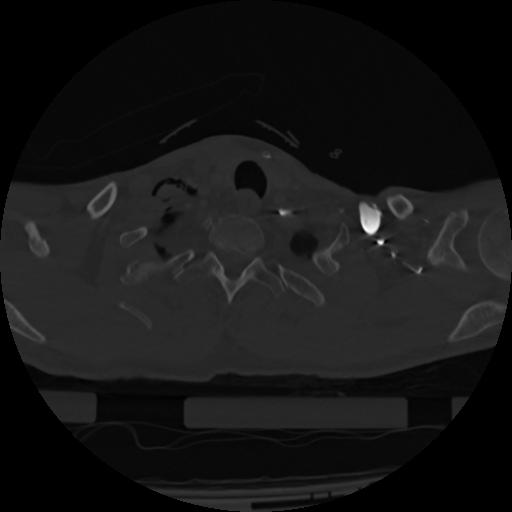

22 ANGIO,CE,Vol,0.5,ANGIO,,